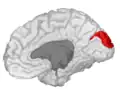

Medial surface of left cerebral hemisphere. (Cuneus visible at left in red.)